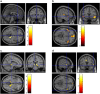

Results: In 4/13 long COVID patients, CT images showed lung abnormalities presenting mild [18F]FDG uptake. Many healthy organs/parenchyma SUVs and SUV ratios significantly differed between the two groups (p ≤ 0.05). Long COVID patients exhibited brain hypometabolism in the right parahippocampal gyrus and thalamus (uncorrected p < 0.001 at voxel level). Specific area(s) of hypometabolism characterised patients with persistent anosmia/ageusia, fatigue, and vascular uptake (uncorrected p < 0.005 at voxel level).

Conclusion: [18F]FDG PET/CT acknowledged the multi-organ nature of long COVID, supporting the hypothesis of underlying systemic inflammation. Whole-body images showed increased [18F]FDG uptake in several "target" and "non-target" tissues. We found a typical pattern of brain hypometabolism associated with persistent complaints at the PET time, suggesting a different temporal sequence for brain and whole-body inflammatory changes. This evidence underlined the potential value of whole-body [18F]FDG PET in disclosing the pathophysiology of long COVID.